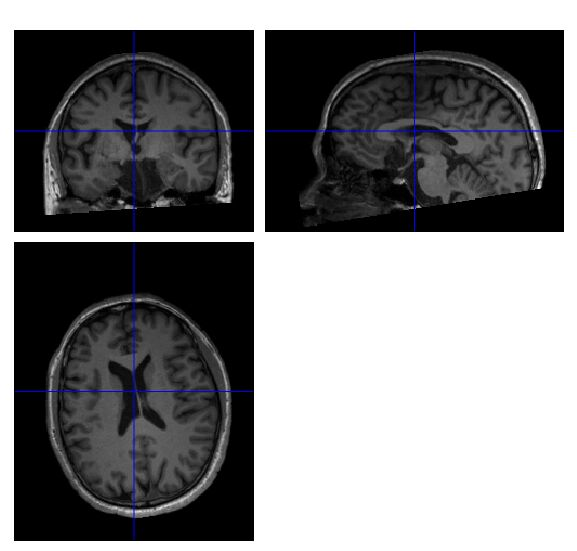

Thank you very much! I convert the DICOM to NIfTI by dcm2nii

previously, not dcm2niix. And I just tried dcm2niix to convert it,

the crop.nii seems no brain tissue were cropped.

1.So I want to ask the if co.nii converted by dcm2nii showed some brain tissue were cropped, is it shouldn't be used for vbm analysis?

2. If crop.nii converted by dcm2niix showed no brain tissue were cropped, can it be used for vbm analysis, since some tools like CAT12 can set orign in the segment preprocess.

I would not use a cropped image if it removes some of the

cerebellum. In general, SPM12/CAT12 are very robust for having

excess neck in the image, as long as they get a good starting

estimate. The origin should be near the anterior commissure. By

default MRI scans use the magnet isocenter as the origin. FSL tends

to be more sensitive to excess neck as this changes the center of

brightness.